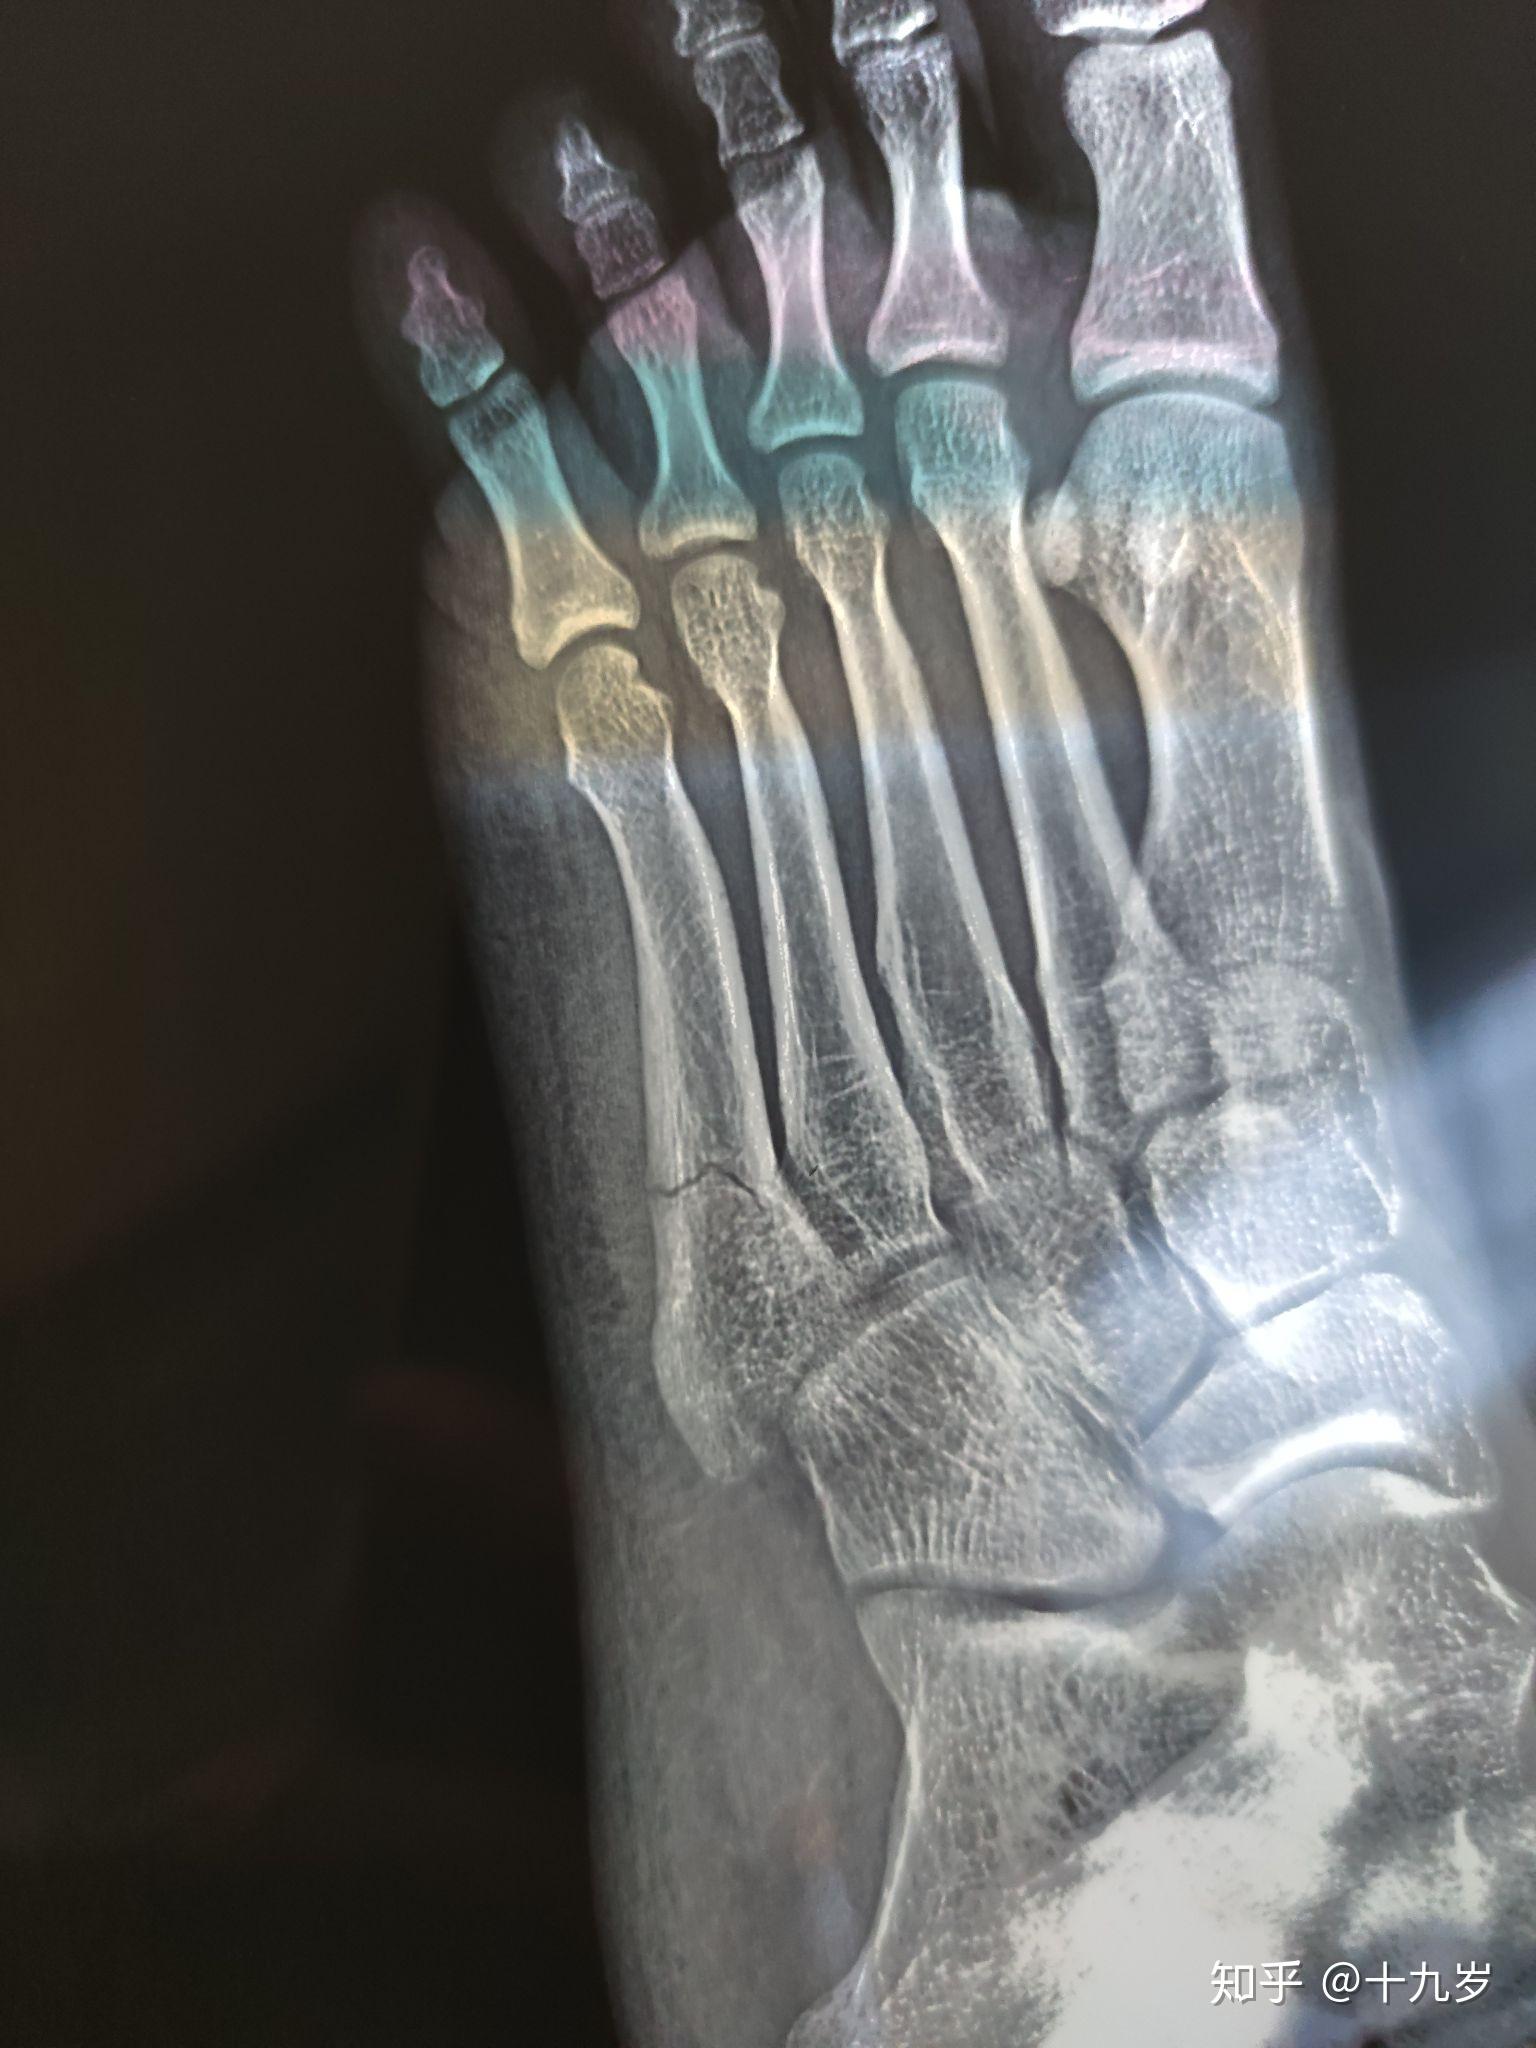

跖骨骨折的x光片

红框标注处,左足第2跖骨陈旧性骨折,骨折线已基本愈合,断端对位对线好